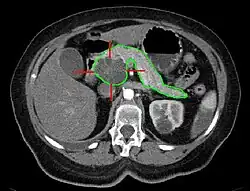

Sonografie, Computertomographie und Kernspintomographie sind die Diagnoseverfahren der Wahl. Aufgabe dieser Methoden ist, Krebserkrankungen von gutartigen Tumoren zu unterscheiden. Weiterhin ist zu erkennen, ob ein Tumor operabel ist. Dies entscheidet sich daran, ob Metastasen vorliegen und ob die dem Pankreas anliegenden Arterien (Arteria mesenterica superior, Truncus coeliacus, Arteria hepatica) von dem Tumor betroffen sind. Die Darstellung der Blutgefäße wird dabei in der Regel durch Gabe von Kontrastmitteln verbessert.